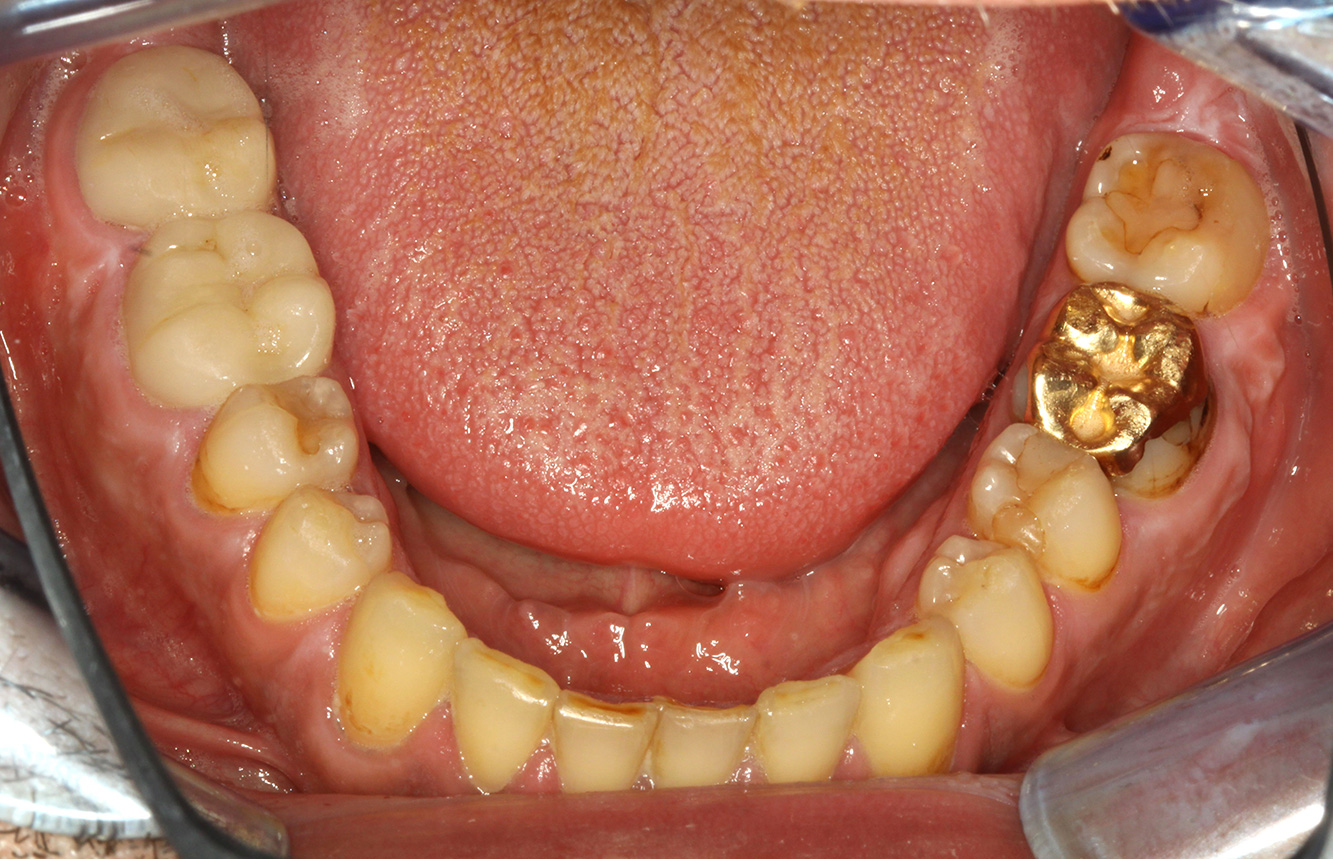

The endocarditis patient with active caries lesions*

The patient is 39 years old and has previously undergone aortic valve replacement due to valve failure and endocarditis. ASS 100 is taken regularly as an anticoagulant. In terms of lifestyle, the patient’s diet is classified as caries-promoting due to the regular consumption of sugary foods and the fact that six to seven meals are consumed daily. The patient’s oral health indicates a moderate risk of caries, with active lesions. The risk of periodontitis is low, but gingivitis is present. The following recommendations are made for prophylactic treatment.

No specific instrument recommendations can be determined for the prophylaxis session. Targeted application of air and rotary polishing can be used to gently reduce plaque and stains on the restoration edges, and to reduce recolonization niches for cariogenic bacteria (19).

Fluoridation is recommended to further support the prevention of caries, and especially to prevent new formation around thethe restoration edges, and to seal the root surfaces. Both of these measures can reduce the teeth’s sensitivity to temperature.

Due to the active caries lesions and the associated risk of progression, a shortened recall interval of three to four months is recommended.